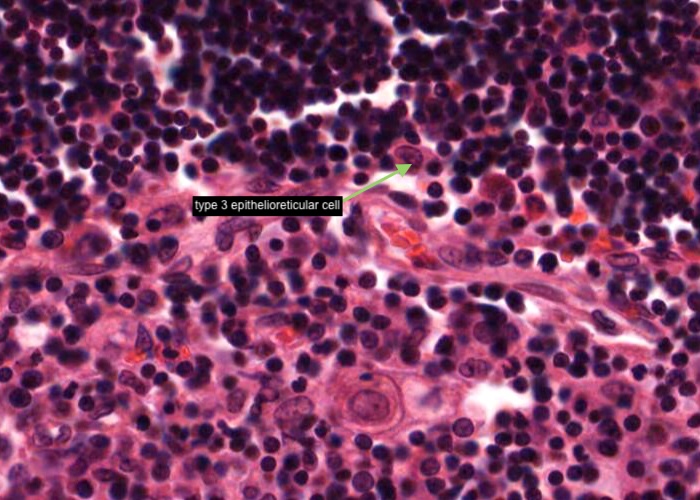

A type III epithelioreticular cell can be seen at the boundary of the cortex and the medulla. They are similar to type 1 cells in functioning as a barrier that isolates developing T- cells between the cortex and medulla.

There are also a substantial number of macrophages in the cortex but you will not be able to distinguish them from epithelial reticular cells in this H&E preparation. If a large pale nucleus has a substantial amount of cytoplasm around it it probably belongs to a macrophage instead of an epithelial reticular cell.